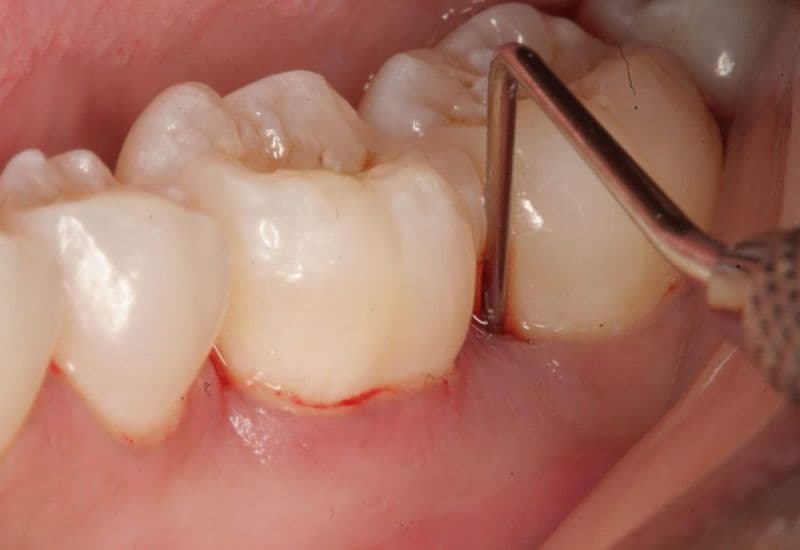

– Lấy cao răng định kỳ:

Đây là bước điều trị cơ bản nhưng rất quan trọng trong việc loại bỏ mảng bám và cao răng – nơi trú ngụ của vi khuẩn gây viêm nướu. Quá trình lấy cao răng không chỉ làm sạch răng mà còn giúp cải thiện tình trạng sưng đỏ, viêm nhiễm ở mô lợi.